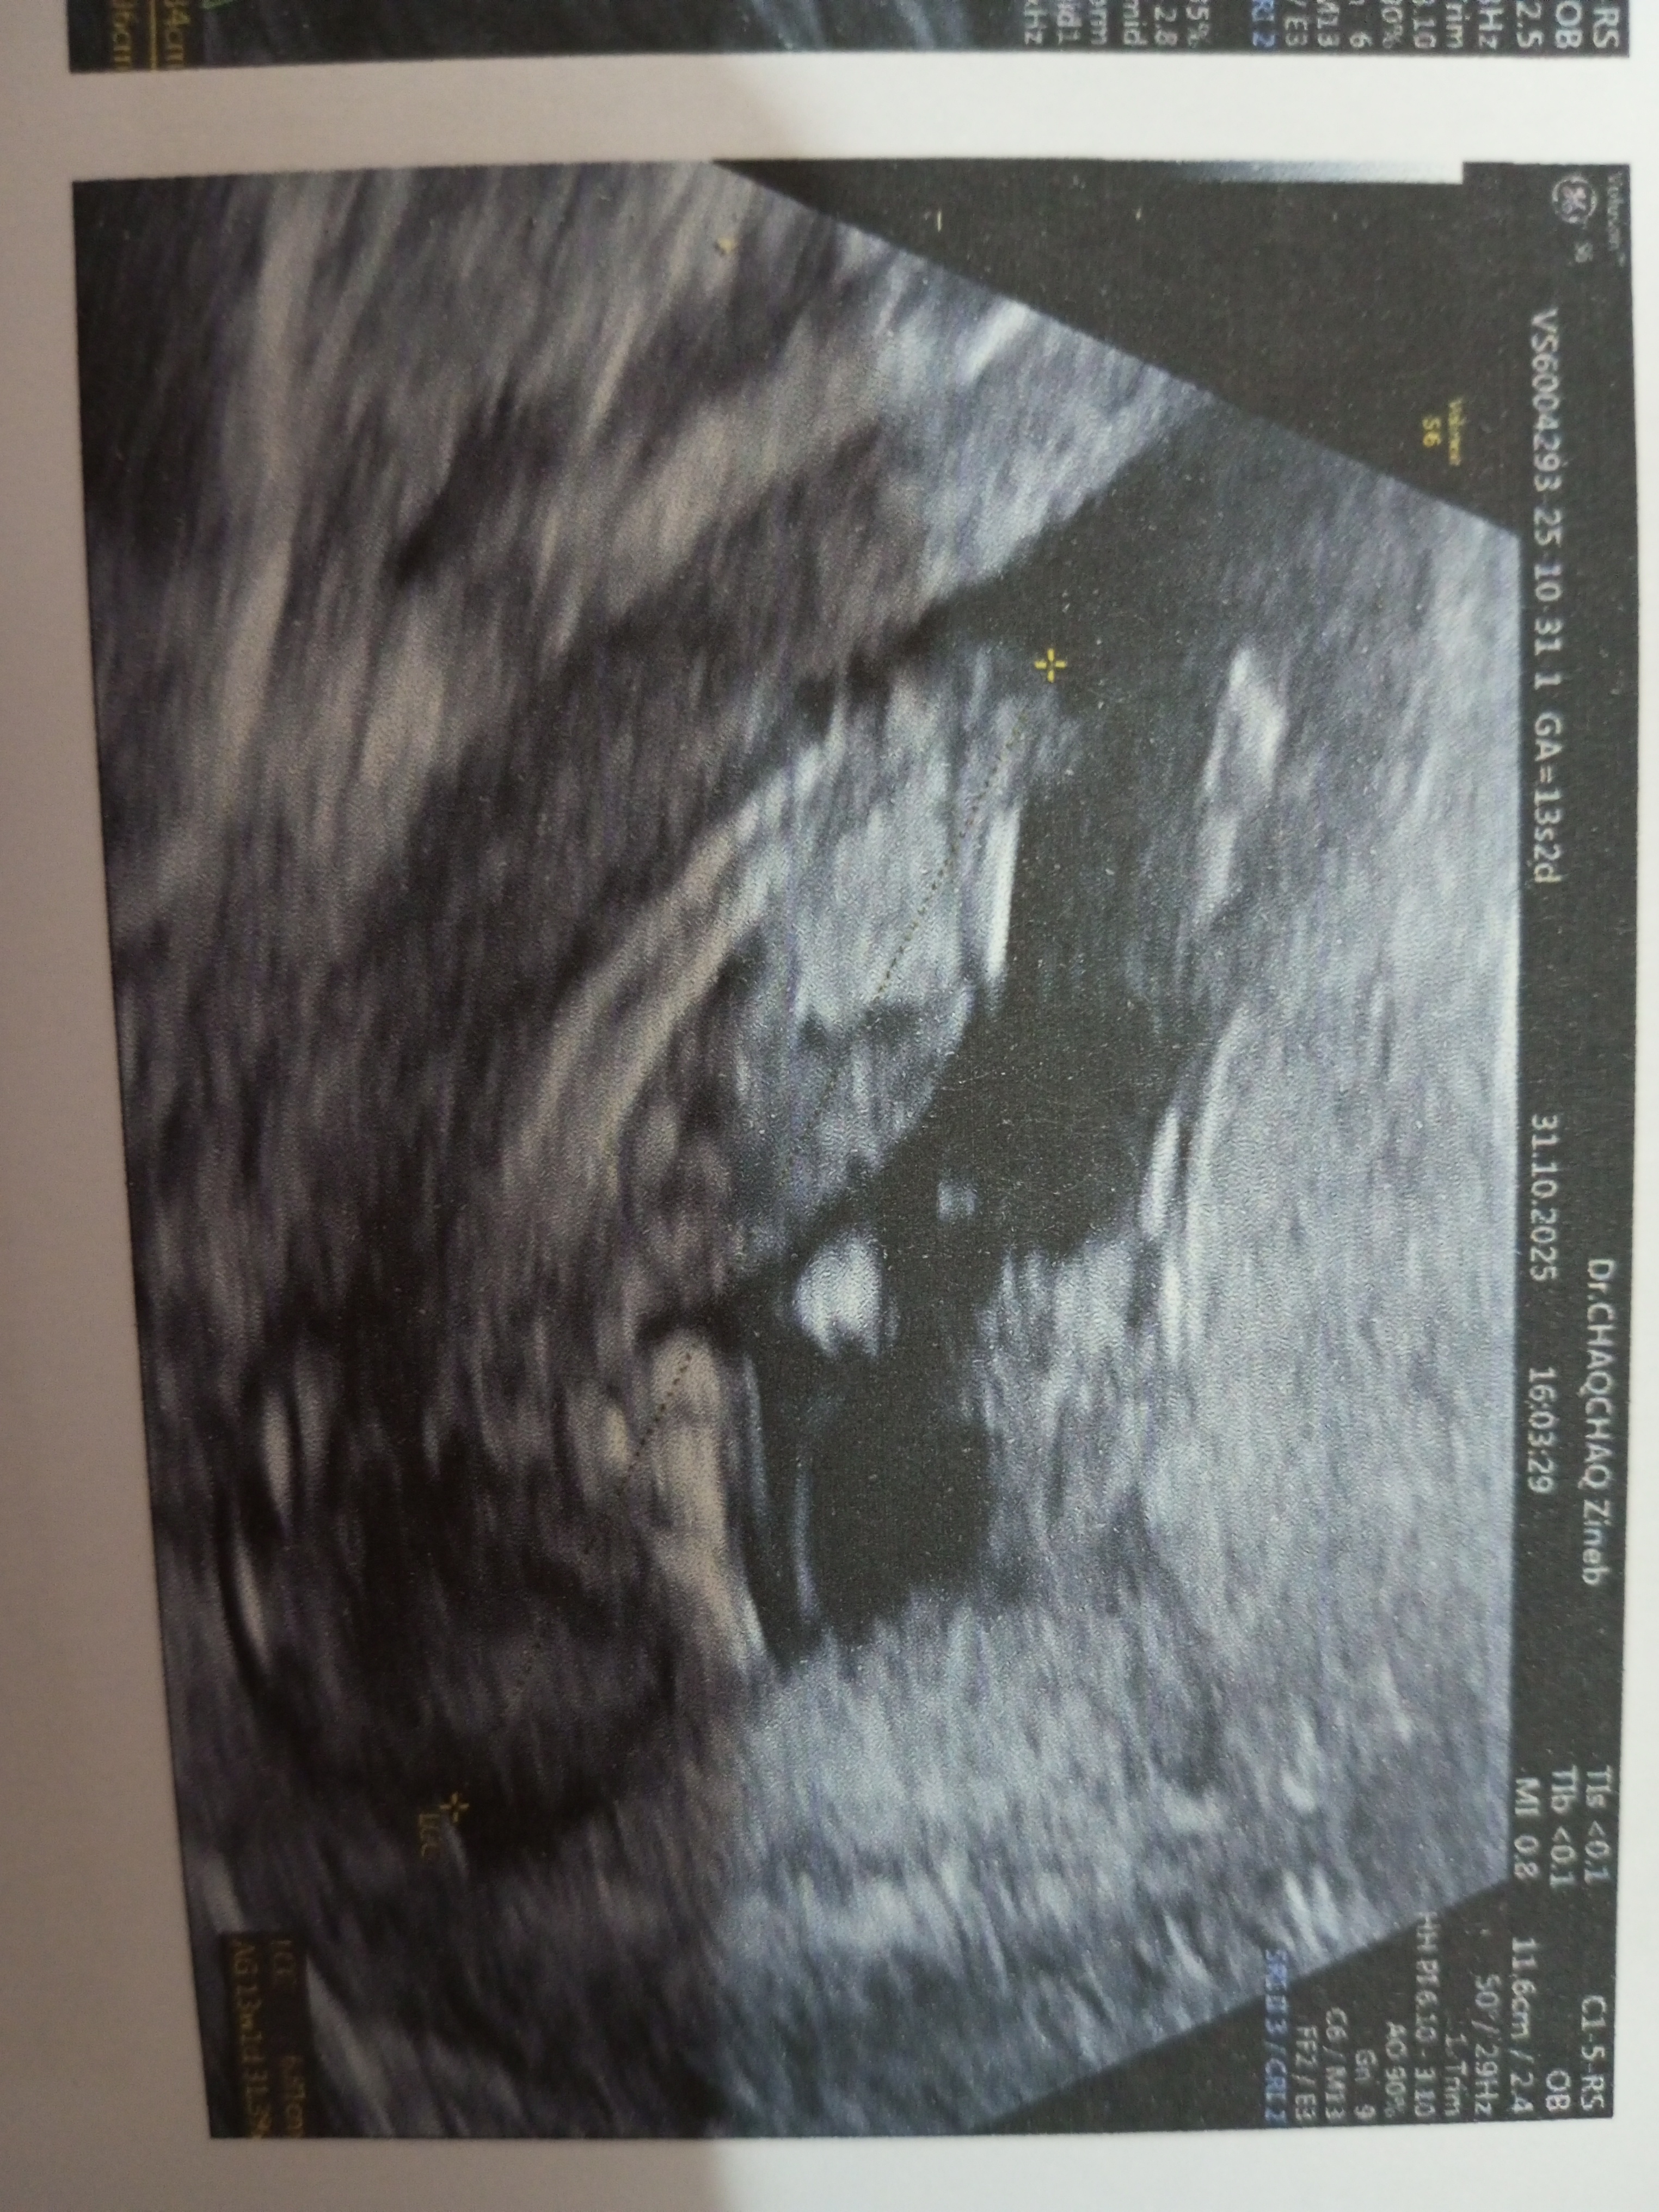

الم في اسفل الحوض واجد كل يوم ماء بني غامق